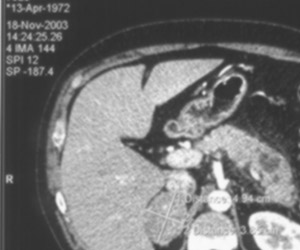

Рис. 2. Для ликвидации муара в процессе сканирования задействована специальная функция Descreen. Ряби на черном фоне уже нет, однако исчезла резость, что особенно хорошо видно по тексту в верхнем левом углу. Связано это с тем, что использовано низкое значения параметра Descreen (100).

Условия сканирования:

Transparent

Grayscale

Bits per color 16,

Разрешение 200,

Descreen 100.